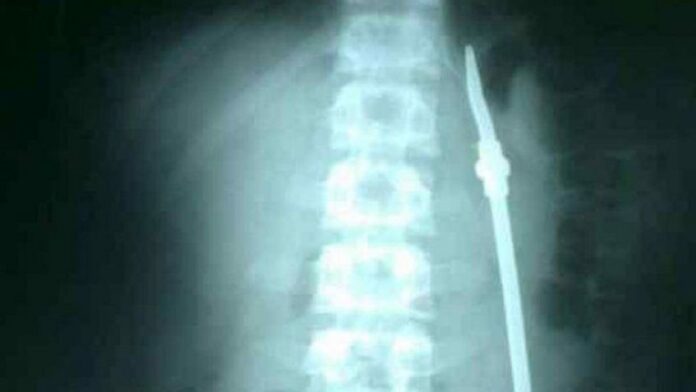

Un preso de 20 años identificado como Olivares, ingresó al hospital San Martín de Paraná, Entre Ríos, tras ingerir una bombilla, luego de tener varios problemas personales, contaron algunos allegados.

En el nosocomio, el paciente debió ser operado de urgencia. Mientras se encontraba en recuperación y con custodia, aprovechó un descuido y se escapó.